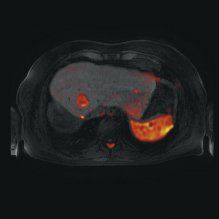

Figure 1 - Follow-up MRI study of cirrhotic patient with previous right hepatectomy for hepatocellular carcinoma. Left: Arterial-phase image does not clearly depict tumor in left liver lobe. Right: Two small recurrent hepatocellular carcinoma foci are evident on fused T1/diffusion-weighted image. Images courtesy of Dr. Caseiro-Alves.

"Because it is not 100% specific, DWI should be interpreted in conjunction with other information from other techniques such as T2-weighted images and contrast enhancement, as well as morphological imaging," he said (see Figure 1).